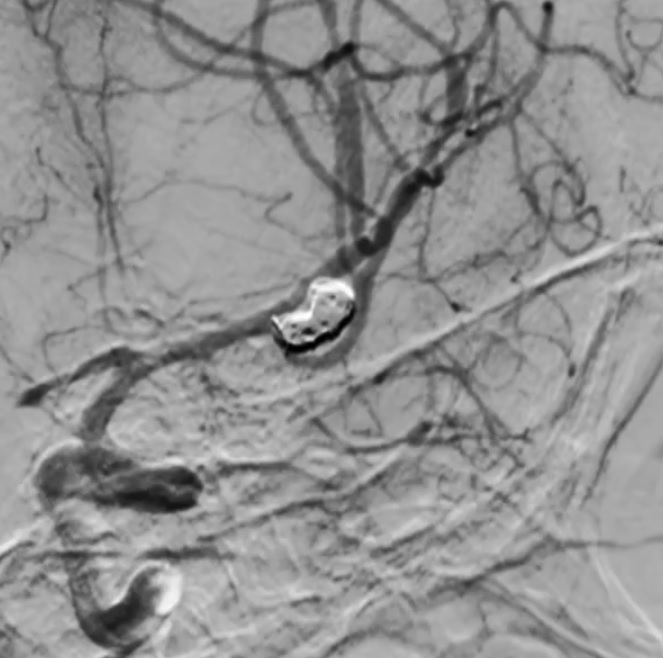

В экстренном порядке пациента направили в операционную. Существовал риск, что орловец останется тяжёлым инвалидом или расстанется с жизнью. Поэтому врачи приняли решение о проведении высокотехнологичной операции – «эмболизации аневризмы с помощью микроспиралей».

Эмболизацией называется процедура, когда медики закупоривают вены и артерии пациенты, чтобы предотвратить кровоснабжение определённых участков организма. Она выполняется малоинвазивным способом, без «широкомасштабного» вторжения в организм. Хирурги оперируют через небольшие надрезы или проколы, иногда через естественные отверстия.